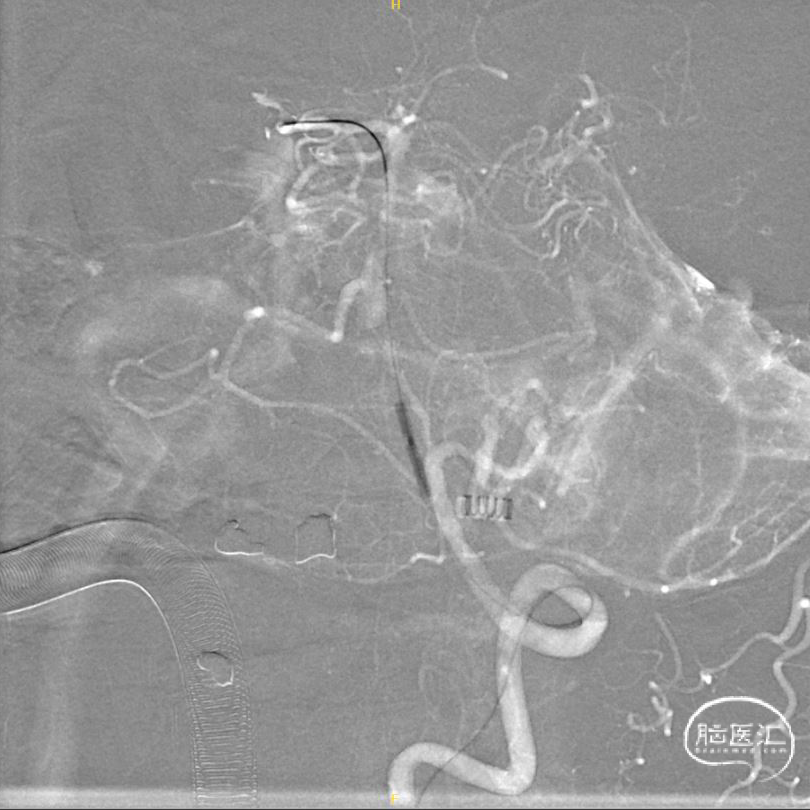

左椎正侧位造影提示:LV4重度狭窄。

右椎正侧位造影提示:RV4以远闭塞,管腔内可见血栓形成。

超选左椎行3D旋转造影。

将6F 导引导管置于左侧椎动脉V2段,调整工作角度,于路图下使用HYBRID 1214DA微导丝轻松将SL-10微导管带过左侧椎动脉V4狭窄段,并置于右侧大脑后动脉。

交换300cm Transend微导丝后,交换1.5*15mm Gateway球囊缓慢扩张。

交换Prowler Plus灌注导管后,沿灌注导管释放4.5*28mm Enterprise支架,交换2.0*9mm Gateway球囊于支架内后扩张。

术后左椎3D旋转造影。